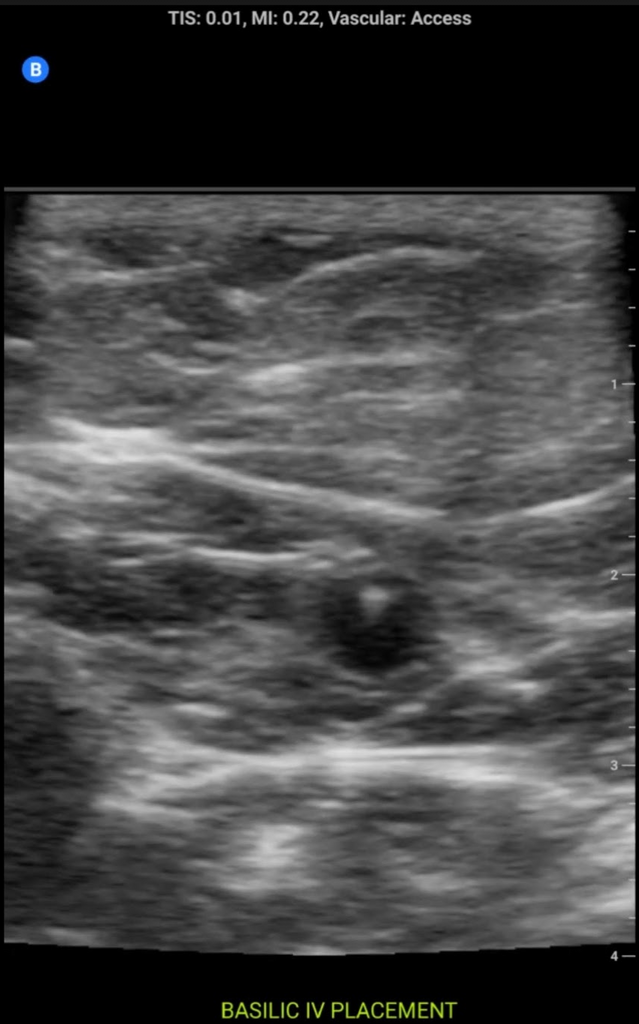

3FA3855F-C446-4231-A200-DC94448A4070.png

Super convenient (butterfly IQ+). U can do tons of nerve blocks, msk injections and even a rough diagnostic msk exam (won’t be able to see things like tendon fiber disorganization, etc, but u can tell if the tendons and ligaments are attached or torn). $3000 and u can buy one with lifetime subscription. It’ll pay for itself relatively quickly.View attachment 327044

Some sample images below:

screenshot.177.pngscreenshot.178.pngscreenshot.180.pngscreenshot.179.png

View attachment 328368View attachment 328369View attachment 328371View attachment 328372

Posting the images help a lot. I wish people with lumify/IQ+ did this more so we could get a better Idea. The pics on the website are def not what u get, but I can do a basic msk exam w these and those require super fine detail. I attached a pic of a posterior horn of the medial meniscus (torn) with a swollen and hypoechoic overlying MCL (meniscofemoral portion) from a patient I just saw. The butterfly is awesome. Unfortunately, I don’t know how to do TTE’s, bladder scans, etc otherwise I would never even consider a lumify.